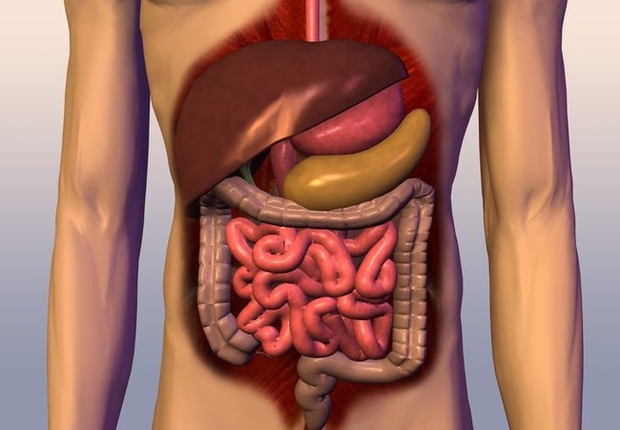

1. Thường xuyên bị táo bón: Ruột chứa cả "ổ rác"

Cơ thể con người có thể mất tới 1-2 ngày để tiêu hóa hết thực phẩm. Trong quá trình đó, các chất dinh dưỡng được giữ lại để nuôi sống các cơ quan nội tạng. Còn các chất cặn bã của thức ăn sẽ tạo thành phân, theo trực tràng thải ra ngoài.

Tuy nhiên, với những người có chức năng tiêu hóa bị trục trặc, các chất cặn bã sẽ không được thải ra trơn tru mà tạo thành táo bón. Táo bón gây đầy bụng, khó chịu cho đường tiêu hóa. Trong trường hợp nghiêm trọng, nó thậm chí có thể làm suy yếu chức năng của các cơ quan khác trong cơ thể và làm giảm sức đề kháng.

2. Cơ thể nhiều mỡ hơn những người khác: Nội tạng chứa "rác"

Mỡ, cholesterol, đạm, đường… là những chất dinh dưỡng cần thiết để nuôi sống cơ thể hàng ngày, nhưng nếu nạp quá mức sẽ trở thành một loại "rác". Việc tích tụ các chất này sẽ gây tăng mỡ thừa ở nội tạng, thậm chí khiến máu bị kết dính, làm xơ cứng thành mạch, dễ gây ra các bệnh hen suyễn, rối loạn nội tiết và các bệnh tim mạch. Từ đó, có thể gây giảm tuổi thọ.